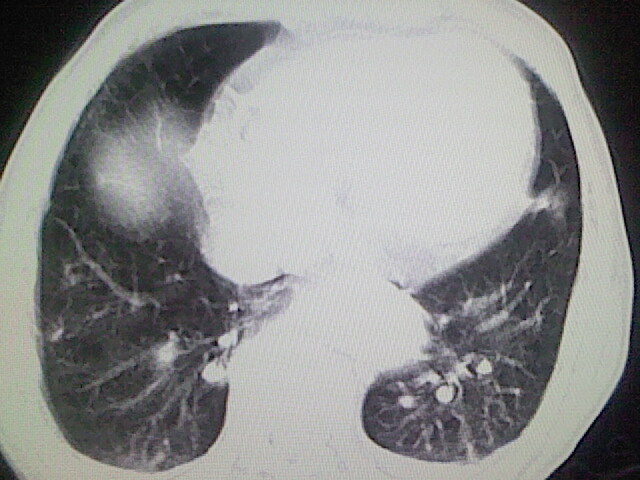

以下是引用zsl6918在2008-8-28 16:49:00的发言:[br]双肺炎性病灶,食管狭窄估计与心房增大压迫所致。

以下是引用xulianj在2008-8-28 20:36:00的发言:[br]慢支肺气肿伴感染,右上肺陈旧性结核;食道建议胃镜检查。

以下是引用wqs571018在2008-8-28 21:18:00的发言:[br]慢支继发感染,右上肺陈旧性结核;食道建议胃镜检查。